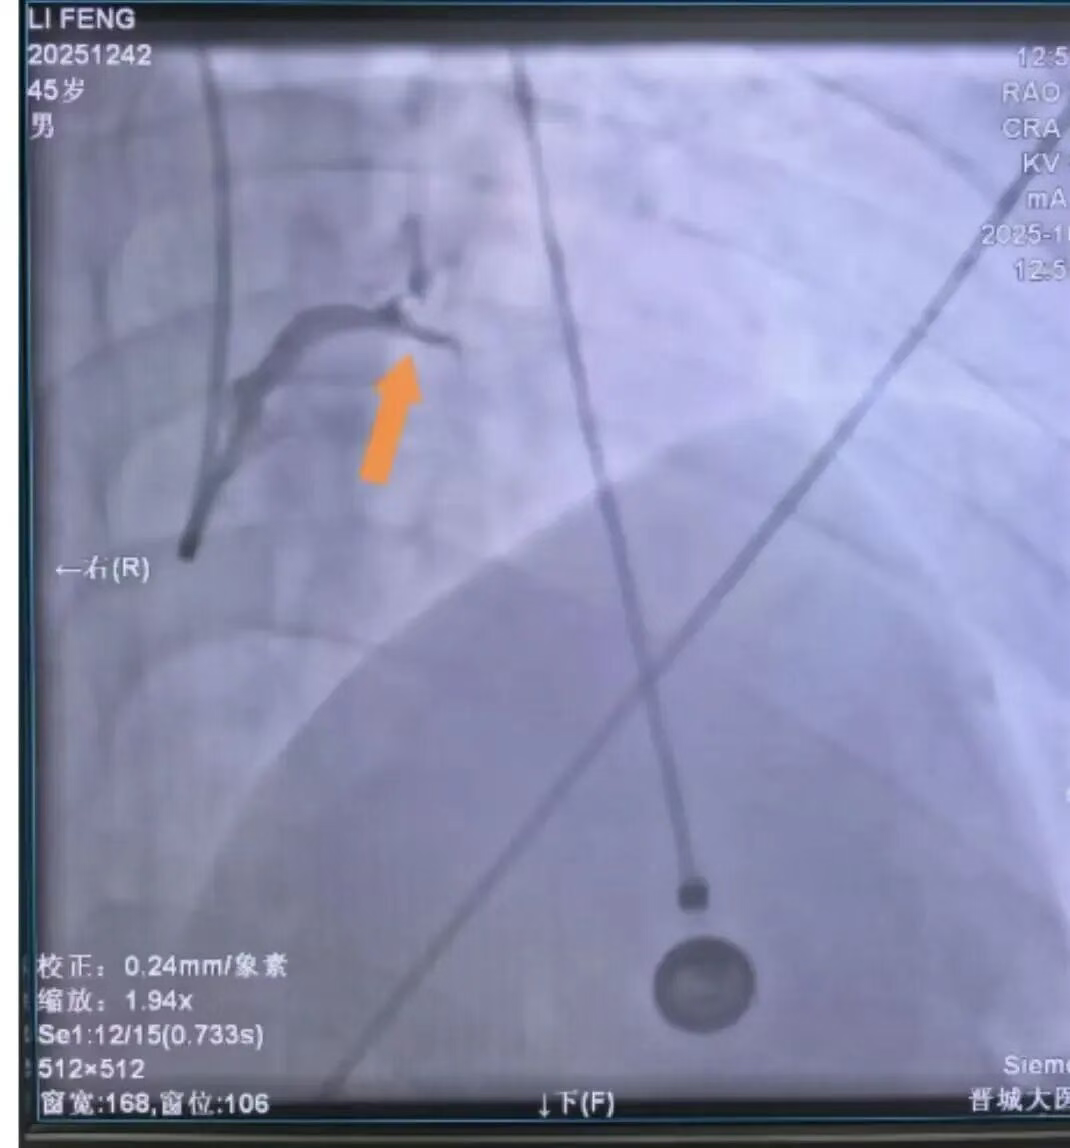

三支主要冠状动脉中,前降支近段完全闭塞,右冠脉亦已闭塞,回旋支近段狭窄达90%,心脏仅靠极微弱的侧支循环维持供血,患者随时可能因心源性休克或恶性心律失常猝死。

手术前